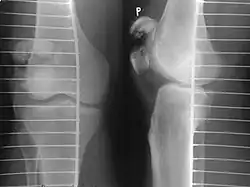

Comminuted fracture of patella -

If the patella is broken in several places, that is comminuted, then traditionally a patellectomy (removal of the whole patella) is performed in order to reconstruct the extensor mechanism and prevent the onset of an extension lag at the knee joint, resulting in instability.[5][8][9] Some surgeons however would rather opt for internal fixation.[8] A partial patellectomy is removal of only a portion of the patella, and may be carried out if at least 60% of the patella can be maintained.[6][8]